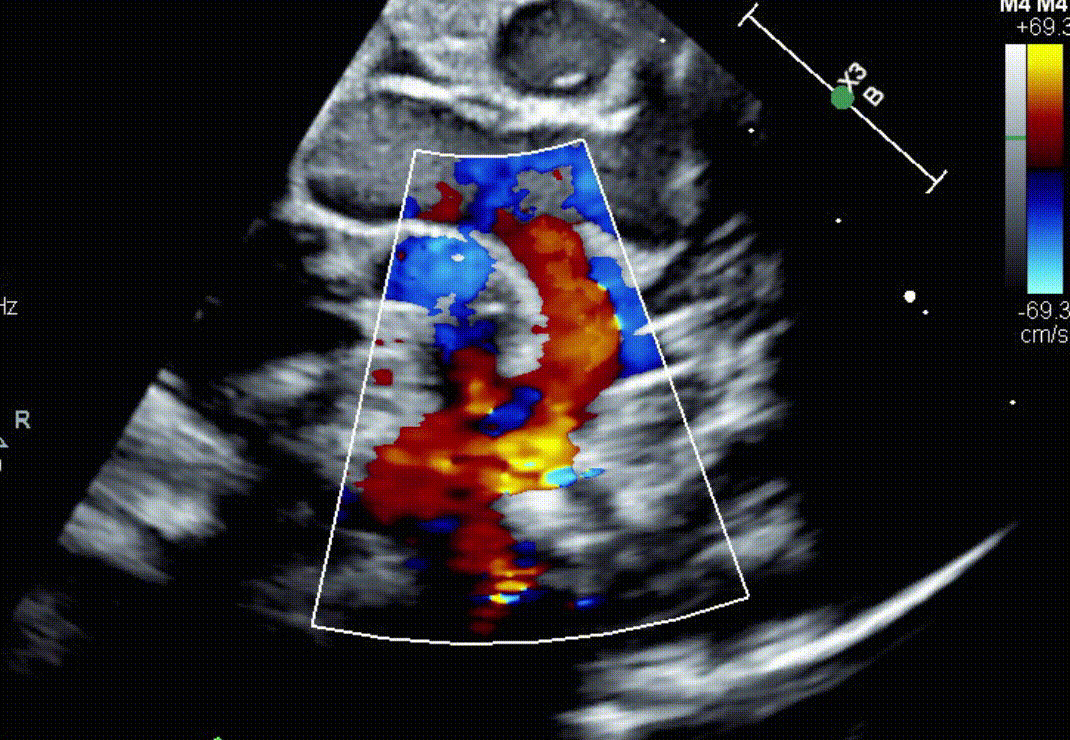

What defect is shown?

What direction is the flow?

What is a bidirectional VSD